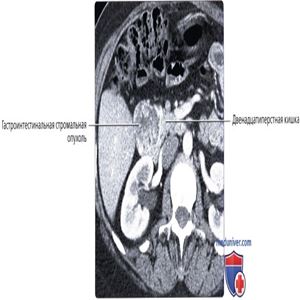

КТ с контрастированием, аксиальный срез: объемное образование с богатым кровоснабжением, растущее из нисходящего/горизонтального отделов двенадцатиперстной кишки. Хотя интенсивно контрастируемое объемное образование в этой области может быть ошибочно принято за нейроэндокринную опухоль поджелудочной железы или карциноидную опухоль двенадцатиперстной кишки, некоторые ГИСО могут интенсивно накапливать контрастное вещество. Это объемное образование было удалено, диагностирована ГИСО.